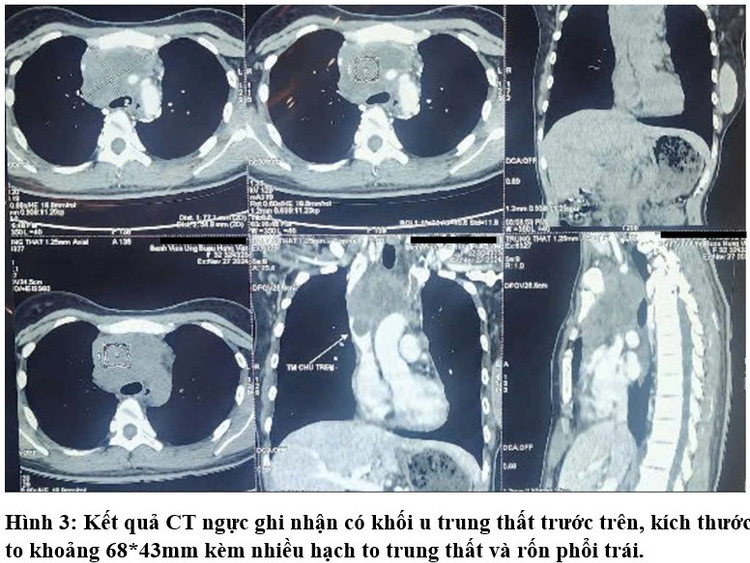

Trường hợp khác, bệnh nhân T. 32 tuổi, (Hà Nội) đi khám vì đau ngực và ho nhiều. Tại đây, bệnh nhân T. được chụp CT ngực. Kết quả ghi nhận bệnh nhân T. có khối u trung thất trước trên với kích thước to khoảng 68*43mm kèm nhiều hạch to trung thất và rốn phổi trái.

Ngay sau đó, bệnh nhân T. đã được ekip bác sĩ bệnh viện Chợ Rẫy tiến hành sinh thiết khối u. Kết quả giải phẫu bệnh là Lymphoma và bệnh nhân đã được điều trị ổn định, quay lại làm việc như trước, may mắn là đã được phát hiện và điều trị kịp thời. Các u lympho thường đáp ứng tốt với hóa trị, vì vậy, tình trạng của bệnh nhân T. được tiên lượng sẽ tốt hơn so với bệnh nhân M.

![]() |